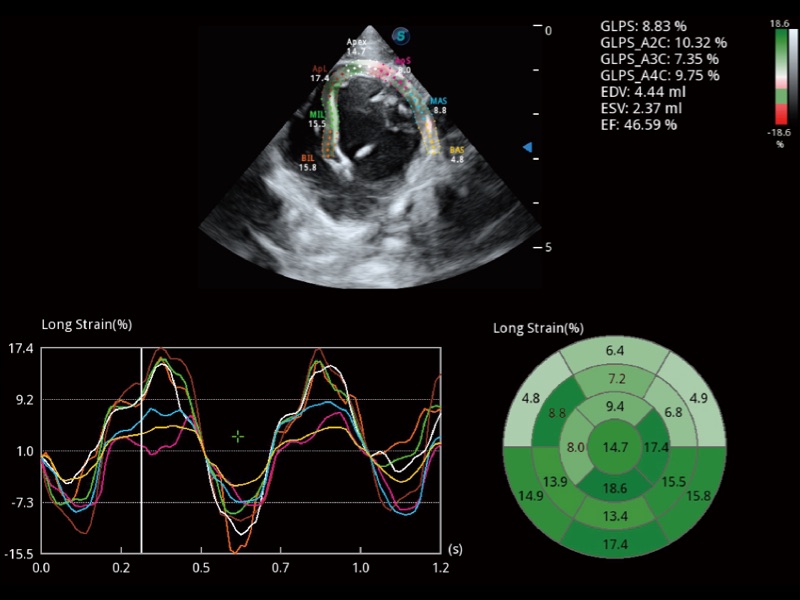

能够基于左心室壁追踪和辛普森法,自动计算射血分数,支持多个可移动点描迹,与手动测量相比,极大节省了动物医生的时间和精力。

实时用颜色表示心肌组织运动,观察和定量组织的运动情况,对快速检测与评估心肌的灌注和活性、电传导及心肌收缩和舒张功能等均能提供重要的诊断信息。

当心脏测量结果超出正常范围时,可实时预警提示动物医生,减少疾病漏诊概率。